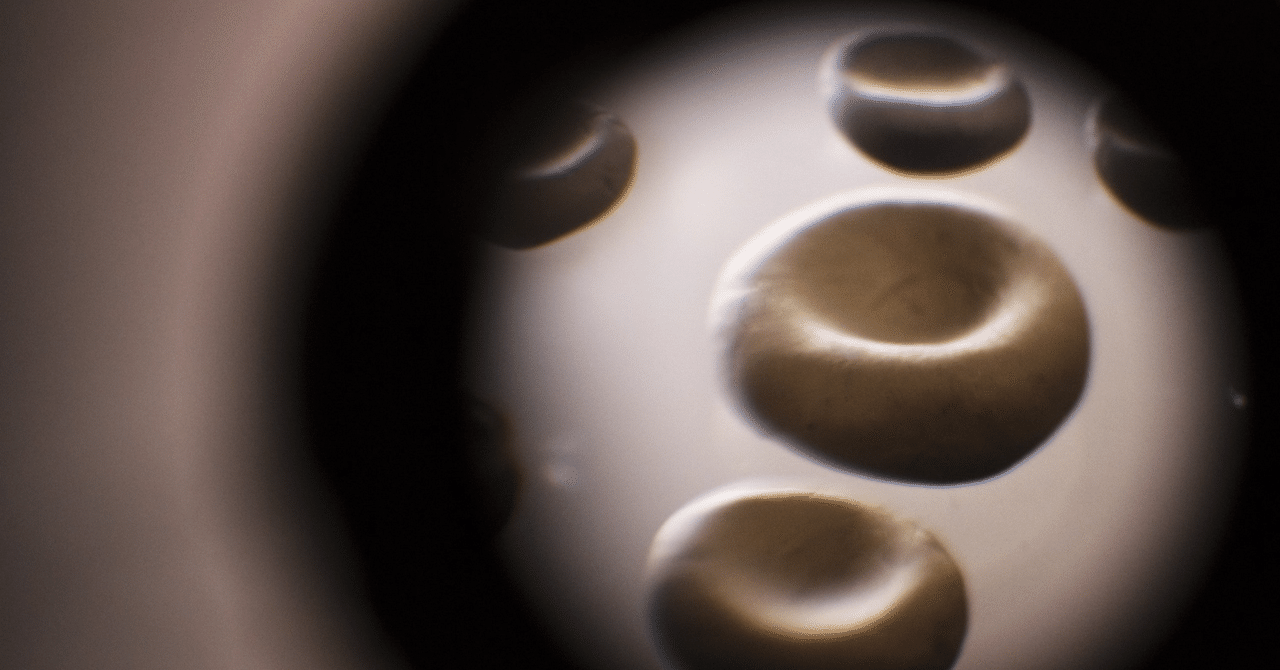

瘀血から線維化現象への推定仮説 瘀血から線維化現象への推定仮説|小池統合医療クリニック 前回に引き続き、マトリックス医学の概略について。いわゆる瘀血の形成から線維化に至る道筋をメモしておきます。 まずは、血管や血球の観察から知れる瘀血の病変について。赤血球の形態変化のしやすさ、連銭の形成状態、プラークの遊離、フィブリンネッツと思われる藻状構造体による血球の捕捉、これらがいわゆる粘性度をあげ、末梢の毛細血管における血流を妨げ、ときに血管外に…note.com

瘀血から線維化現象への推定仮説|小池統合医療クリニック 前回に引き続き、マトリックス医学の概略について。いわゆる瘀血の形成から線維化に至る道筋をメモしておきます。 まずは、血管や血球の観察から知れる瘀血の病変について。赤血球の形態変化のしやすさ、連銭の形成状態、プラークの遊離、フィブリンネッツと思われる藻状構造体による血球の捕捉、これらがいわゆる粘性度をあげ、末梢の毛細血管における血流を妨げ、ときに血管外に…note.com